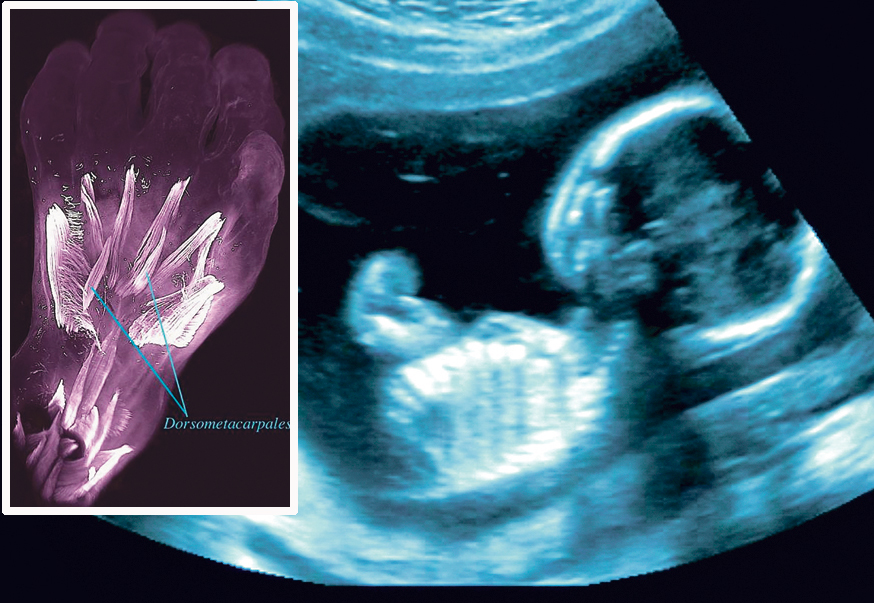

Ilustracija

Planirani carski rez može biti najsigurnija opcija za žene koje su i ranije rodile na taj način, rezultati su istraživanja objavljeni u časopisu PLoS medicine.

Vaginalni porođaj nakon carskog reza povezan je s većim izgledima za razvoj komplikacija. Znanstvenici su do ovakvog saznanja došli nakon rezultata istraživanja o 74.000 porođaja u Škotskoj, piše BBC.